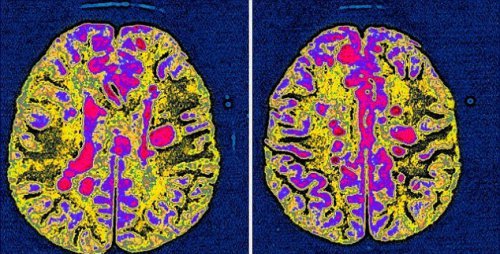

Парализованные из-за рассеянного склероза пациенты снова смогли ходить благодаря инъекциям стволовых клеток. Таковы результаты уникального исследования, проведенного в Великобритании.

Парализованные из-за прогрессирующего рассеянного склероза пациенты не смогли сдержать радости, когда снова встали на ноги благодаря инъекциям стволовых клеток, которые обычно применяются в лечении рака. Примерно 20 человек прошли через трансплантацию костного мозга с использованием собственных стволовых клеток в ходе клинических исследований в Royal Hallamshire Hospital Шеффилда, которые также проводятся в США, Швеции и Бразилии.

На первом этапе их поврежденная иммунная система была уничтожена химиотерапией. Зачем врачи восстановили ее с помощью инъекций стволовых клеток, которые были собраны из собственной крови пациентов. Сообщество помощи жертвам рассеянного склероза назвало результаты этих клинических исследований колоссальными, однако предупредило, что подобное лечение является очень агрессивным, и может не подойти всем жертвам болезни.

Но лишившиеся подвижности из-за прогрессирующего нейродегенеративные заболевания пациенты смогли встать без посторонней помощи, пойти пешком, покататься на велосипеде и даже поплавать после трансплантации. Провести лечение, которое способно повернуть вспять неизлечимое тяжелейшие заболевания, это большое достижение ученых. Данная терапия носит название трансплантация аутогенных гемопоэтических стволовых клеток

Рассеянным склерозом болеют приблизительно в три раза больше женщин, чем мужчин. Как правило, диагноз ставится в возрасте от 20 до 40 лет. Среди симптомов - изматывающая усталость, онемение и дрожь конечностей, проблемы со зрением и нарушения походки, однако болезнь развивается у каждого человека по-разному. Один из пациентов (на 4 фото), принявших участие в исследовании, когда-то пробегал марафон, а на последнем этапе болезни уже не мог держать ложку в руках. И вот теперь он снова встал на ноги.